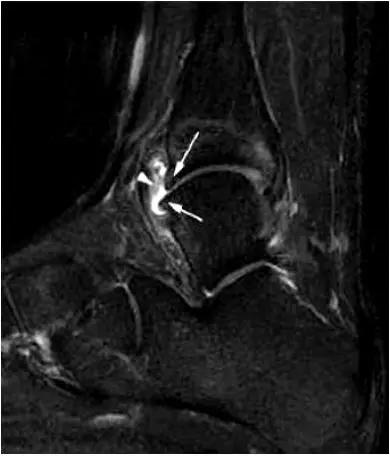

- 影像学表现为距骨后三角骨的存在或损伤以及距骨后突骨赘形成,导致踝关节跖屈受限,可伴随拇长屈肌肌腱鞘炎症及邻近滑膜不同程度的炎性增生 。

- MRI 检查示距后三角骨及周围软组织有水肿信号,距后三角骨和距骨之间正常的低信号纤维连接中断,出现液性信号。

- 三角籽骨或距骨后三角结构模糊和变形,T1WI信号降低, T2WI信号升高,

- 周围脂肪水肿,

- 踇趾长屈肌腱信号升高,见鞘膜积液,

- 胫骨后下跟骨上缘骨结构形态变化和信号异常,

- 三角籽骨和距骨退行性囊变。

三角籽骨综合征

三角籽骨综合征并跟腱滑囊积液